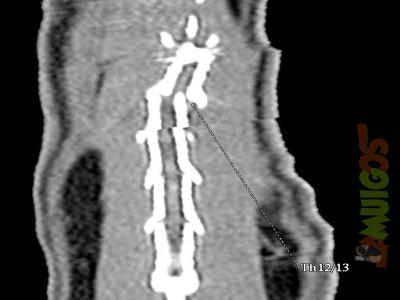

| Fotoalben > "Moderne diagnostische Methoden in der Heimtiermedizin" | ![]() |